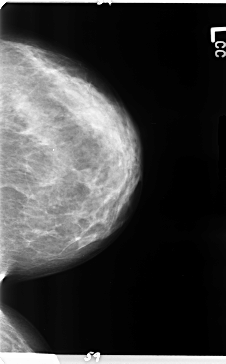

ics_version 1.0 filename B-3157-1 DATE_OF_STUDY 9 6 1997 PATIENT_AGE 42 FILM FILM_TYPE REGULAR DENSITY 2 DATE_DIGITIZED 5 5 1998 DIGITIZER LUMISYS LASER SEQUENCE LEFT_CC LINES 4720 PIXELS_PER_LINE 2928 BITS_PER_PIXEL 12 RESOLUTION 50 NON_OVERLAY LEFT_MLO LINES 4736 PIXELS_PER_LINE 2704 BITS_PER_PIXEL 12 RESOLUTION 50 NON_OVERLAY RIGHT_CC LINES 4704 PIXELS_PER_LINE 2800 BITS_PER_PIXEL 12 RESOLUTION 50 OVERLAY RIGHT_MLO LINES 4672 PIXELS_PER_LINE 3032 BITS_PER_PIXEL 12 RESOLUTION 50 OVERLAY |

FILE: B_3157_1.RIGHT_CC.OVERLAY TOTAL_ABNORMALITIES 1 ABNORMALITY 1 LESION_TYPE MASS SHAPE LOBULATED MARGINS CIRCUMSCRIBED ASSESSMENT 4 SUBTLETY 4 PATHOLOGY BENIGN TOTAL_OUTLINES 1 BOUNDARY |